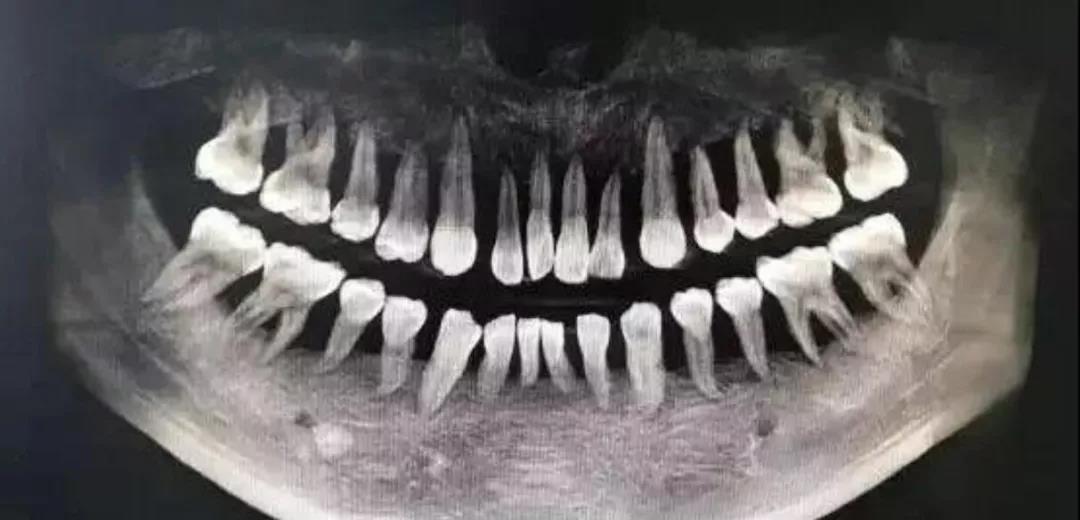

一名90后姑娘,轻度牙周炎6年发展为重度,上半口牙全部松动被拔光,而拔牙只是第一步,她还得种牙,要花费十五六万元。

杭州25岁小伙患重度牙周炎,整口牙松动明显,牙齿状况堪比80岁的老太太,同样面临全口牙拔除的困境……